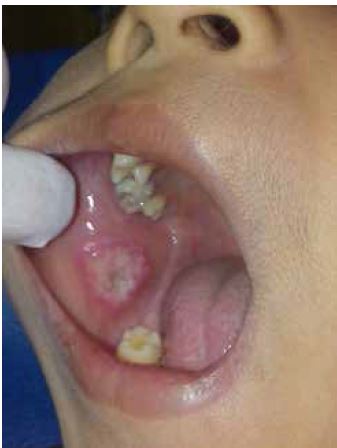

Se indicó a los padres los cuidados que debían tener con el niño, sobre todo haciendo insistencia a que estuvieran pendientes de que el mismo no se mordiera. Aproximadamente a las 24 horas de realizada la exodoncia concurren nuevamente a la consulta por dolor, los padres manifestaban que era por la extracción de la pieza dentaria; A la inspección clínica intraoral del niño se observó en la mucosa yugal del lado derecho, una lesión única, con fondo necrótico, color blanco amarillento, cubierta por un exudado fibrinoso, de forma redondeada, con bordes irregulares y márgenes definidos, rodeada de un halo eritematoso. Sus dimensiones eran aproximadamente 20mm de diámetro. El niño refería sintomatología dolorosa durante la masticación y el cepillado dental.

Al interrogatorio el niño, relata que no sentía nada cuando se mordía, por lo que se estima que provoco curiosidad, este movimiento de mordisqueo provocó en la parte central de la mucosa yugal derecha, una ulcera con la impronta de la pieza dentaria 4.6 (figura 1 y figura 2).

Al examen clínico intraoral, se observó en la mucosa y semimucosa del labio inferior en el sector derecho, una lesión de forma irregular con márgenes definidos, elevada, de coloración blanquecina, rodeada por un halo eritematoso en la periferia, sus dimensiones abarcaban más de la mitad de labio inferior, con sintomatología dolorosa urente (figura 3).